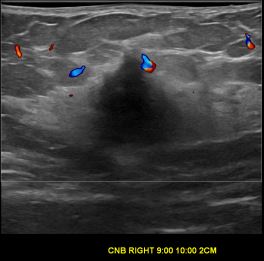

상기환자는 우측 만져지는 멍울과 통증있어 검사위해 내원하신 50대 중반

여성분으로 의심스러운 우측유방혹 조직검사 시행해 유방암으로 진단되었습니다